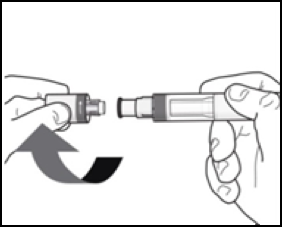

4. Entfernen Sie die Kappe: